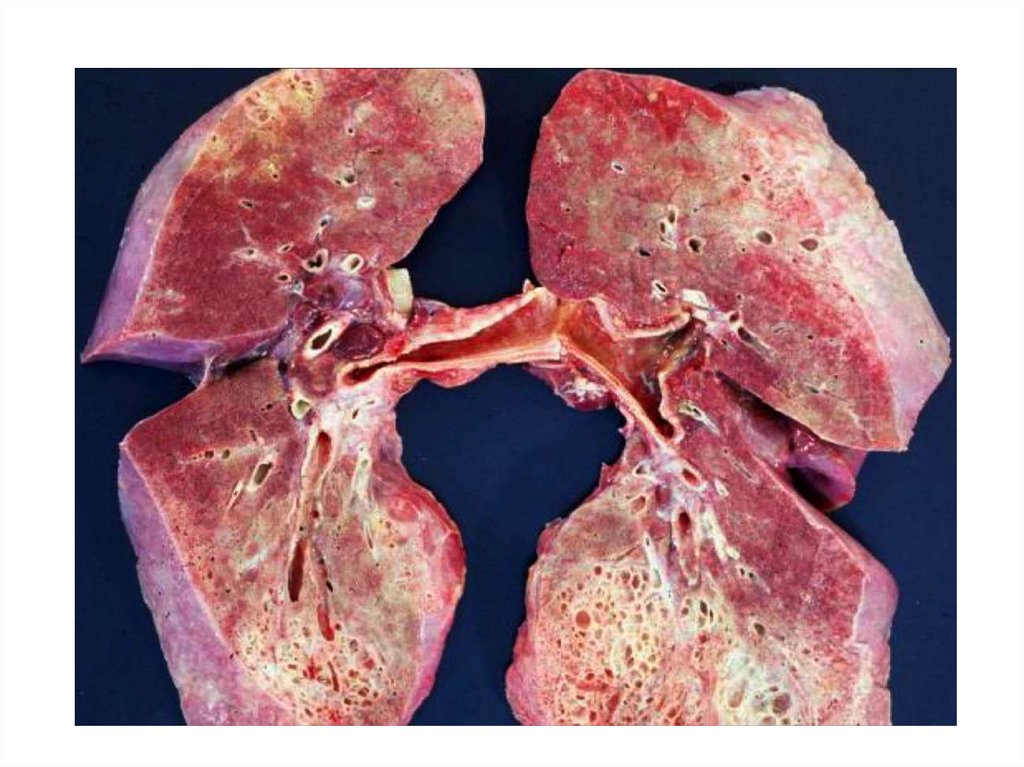

32. Стеноз митрального отверстия

33. Далеко зашедшая форма стеноза митрального отверстия